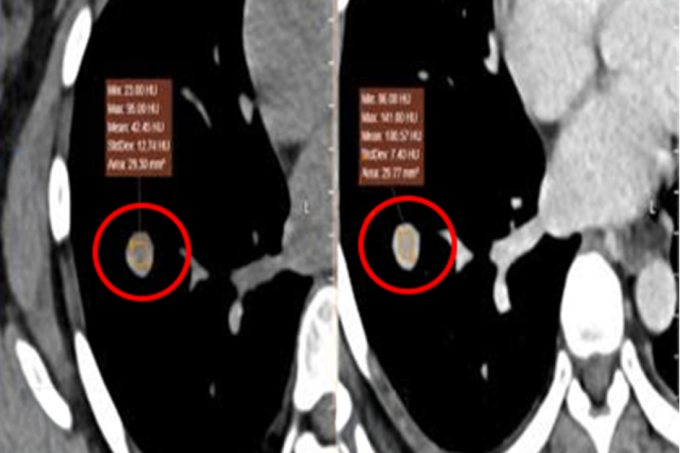

Kết quả nội soi dạ dày bệnh nhân tại Bệnh viện Đa khoa Tâm Anh TP HCM cho thấy viêm xước ở niêm mạc hang vị mức độ nhẹ, khối u dưới niêm ở vị trí 1/3 dưới thực quản, kích thước 2,5 cm. Ảnh nội soi siêu âm ghi nhận u nằm ở lớp cơ niêm (lớp thứ hai của ống tiêu hóa), hình móng ngựa (vòng cung giống chiếc móng ngựa), không tăng sinh mạch, tức là chưa có khả năng xâm lấn các mô lân cận.

Tiến sĩ, bác sĩ Đỗ Minh Hùng, Giám đốc Trung tâm Nội soi và phẫu thuật Nội soi Tiêu hóa, cho biết tổn thương dưới niêm của chị Phương là u cơ trơn hình móng ngựa, chiếm 0,5-1% khối u thực quản. Đây là một loại u lành tính nhưng vẫn có thể biến chứng nguy hiểm nếu u phát triển lớn gây nuốt nghẹn, đau tức ngực, đau sau xương ức, nôn ói.